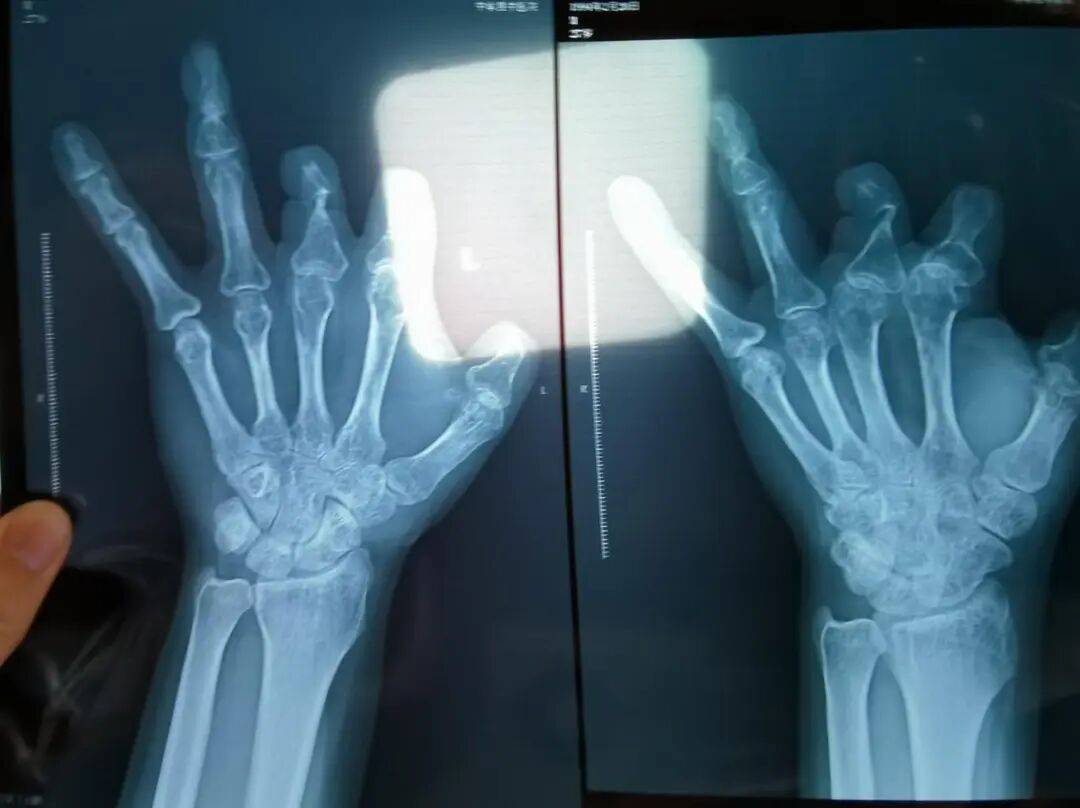

▲患者王海森左手拇指关节以上部位被电锯切断,收费单显示术中使用了微血管吻合装置,但X光片中未显示该器械。新京报记者 程亚龙 摄

该产品的代理商曾向新京报记者证实,微血管吻合装置为植入型医疗器材,患者拍摄X光片时会有显示。新京报记者获取了一位曾在郑大一附院接受手术、使用了该产品的患者的X光片,其手术部位可见一绿豆大小的光圈。

王海森称,他出院约1年后,有人曾找到他说,这个价格昂贵的进口器材,并没有在手术中使用。当时他没有相信,直到2021年12月,经人提醒,王海森在老家开封尉氏县人民医院拍摄了左手X光片,才确认手术部位的确没有微血管吻合装置。2021年12月底,王海森向郑州市公安局二七分局刑侦大队报案。

▲2021年12月,患者彭先生拍摄的左手X光片,未见收费单据中列出的微血管吻合装置。新京报记者 程亚龙 摄

法院判定,多名被害人证明,其术后接受X光检查,体内均无该装置。94名被害人中,有多名1岁、5岁、6岁不等的儿童因手指创伤接受微血管吻合装置治疗,相比成人血管粗细程度,更能证明该治疗行为的虚假性。在手术过程中,王福建明知多名患者不符合使用微血管吻合装置的条件,又隐瞒未实际使用的事实,将该医疗器械的费用,计入患者的收费清单,致被害人超额支付医疗费用。